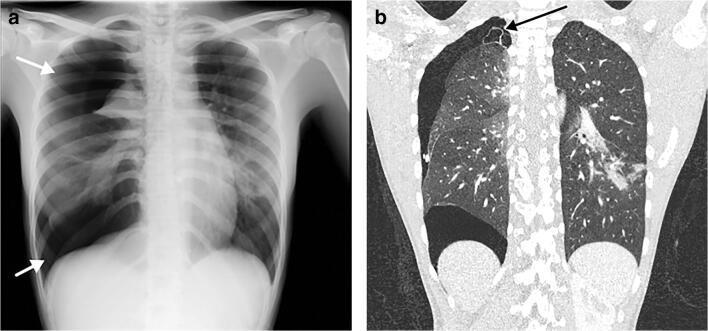

Pediatric COVID-19: MIS-C

Thoracic abnormalities

Cardiovascular abnormalities

Cardiomegaly

CHF or cardiogenic edema

Pulmonary parenchymal abnormalities

Lower lobe atelectasis

Bilateral opacities( ARDS)

Consolidation

Pleural abnormalities

Small pleural effusion

Mediastinal and hilar lymphadenopathy

MIS-C Embolism

MIS-C: Heart failure

60 Embolus Imaging of Covid 19 infection in children